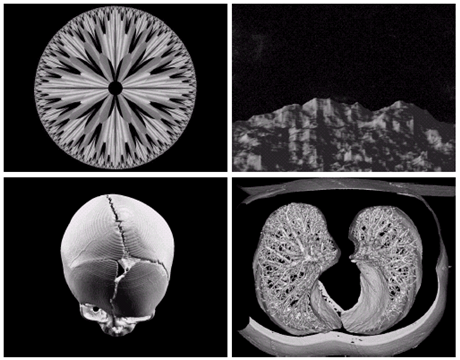

Gamma ray image

- 감마선의 투과성을 이용

- 주요 응용분야: 핵의학, 천문관측

a) 환자에게 감마선을 방사하는 방사선 동위원소를 주사, 감마 검출기로써 영상을 획득 - 병소의 위치 파악에 유용

b) PET(positron emission tomography) image

c) 백조자리 15,000년전의 가스성운의 감마선 영상

d) 핵반응 밸브로부터 나오는 감마선(밝은 부분)

X-ray image